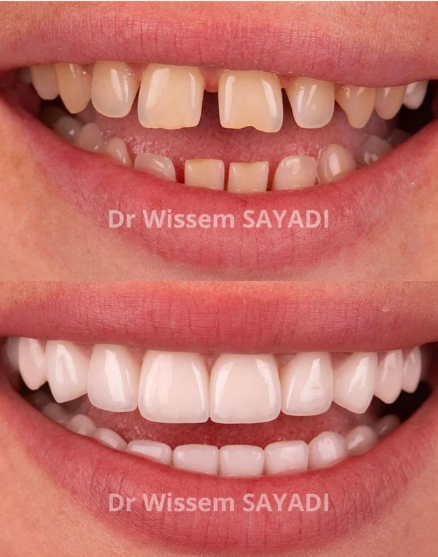

Votre sourire, notre priorité

Dents Saines,

Vie Sereine

Soins dentaires d'excellence en Tunisie.

Qualité européenne, tarifs accessibles.